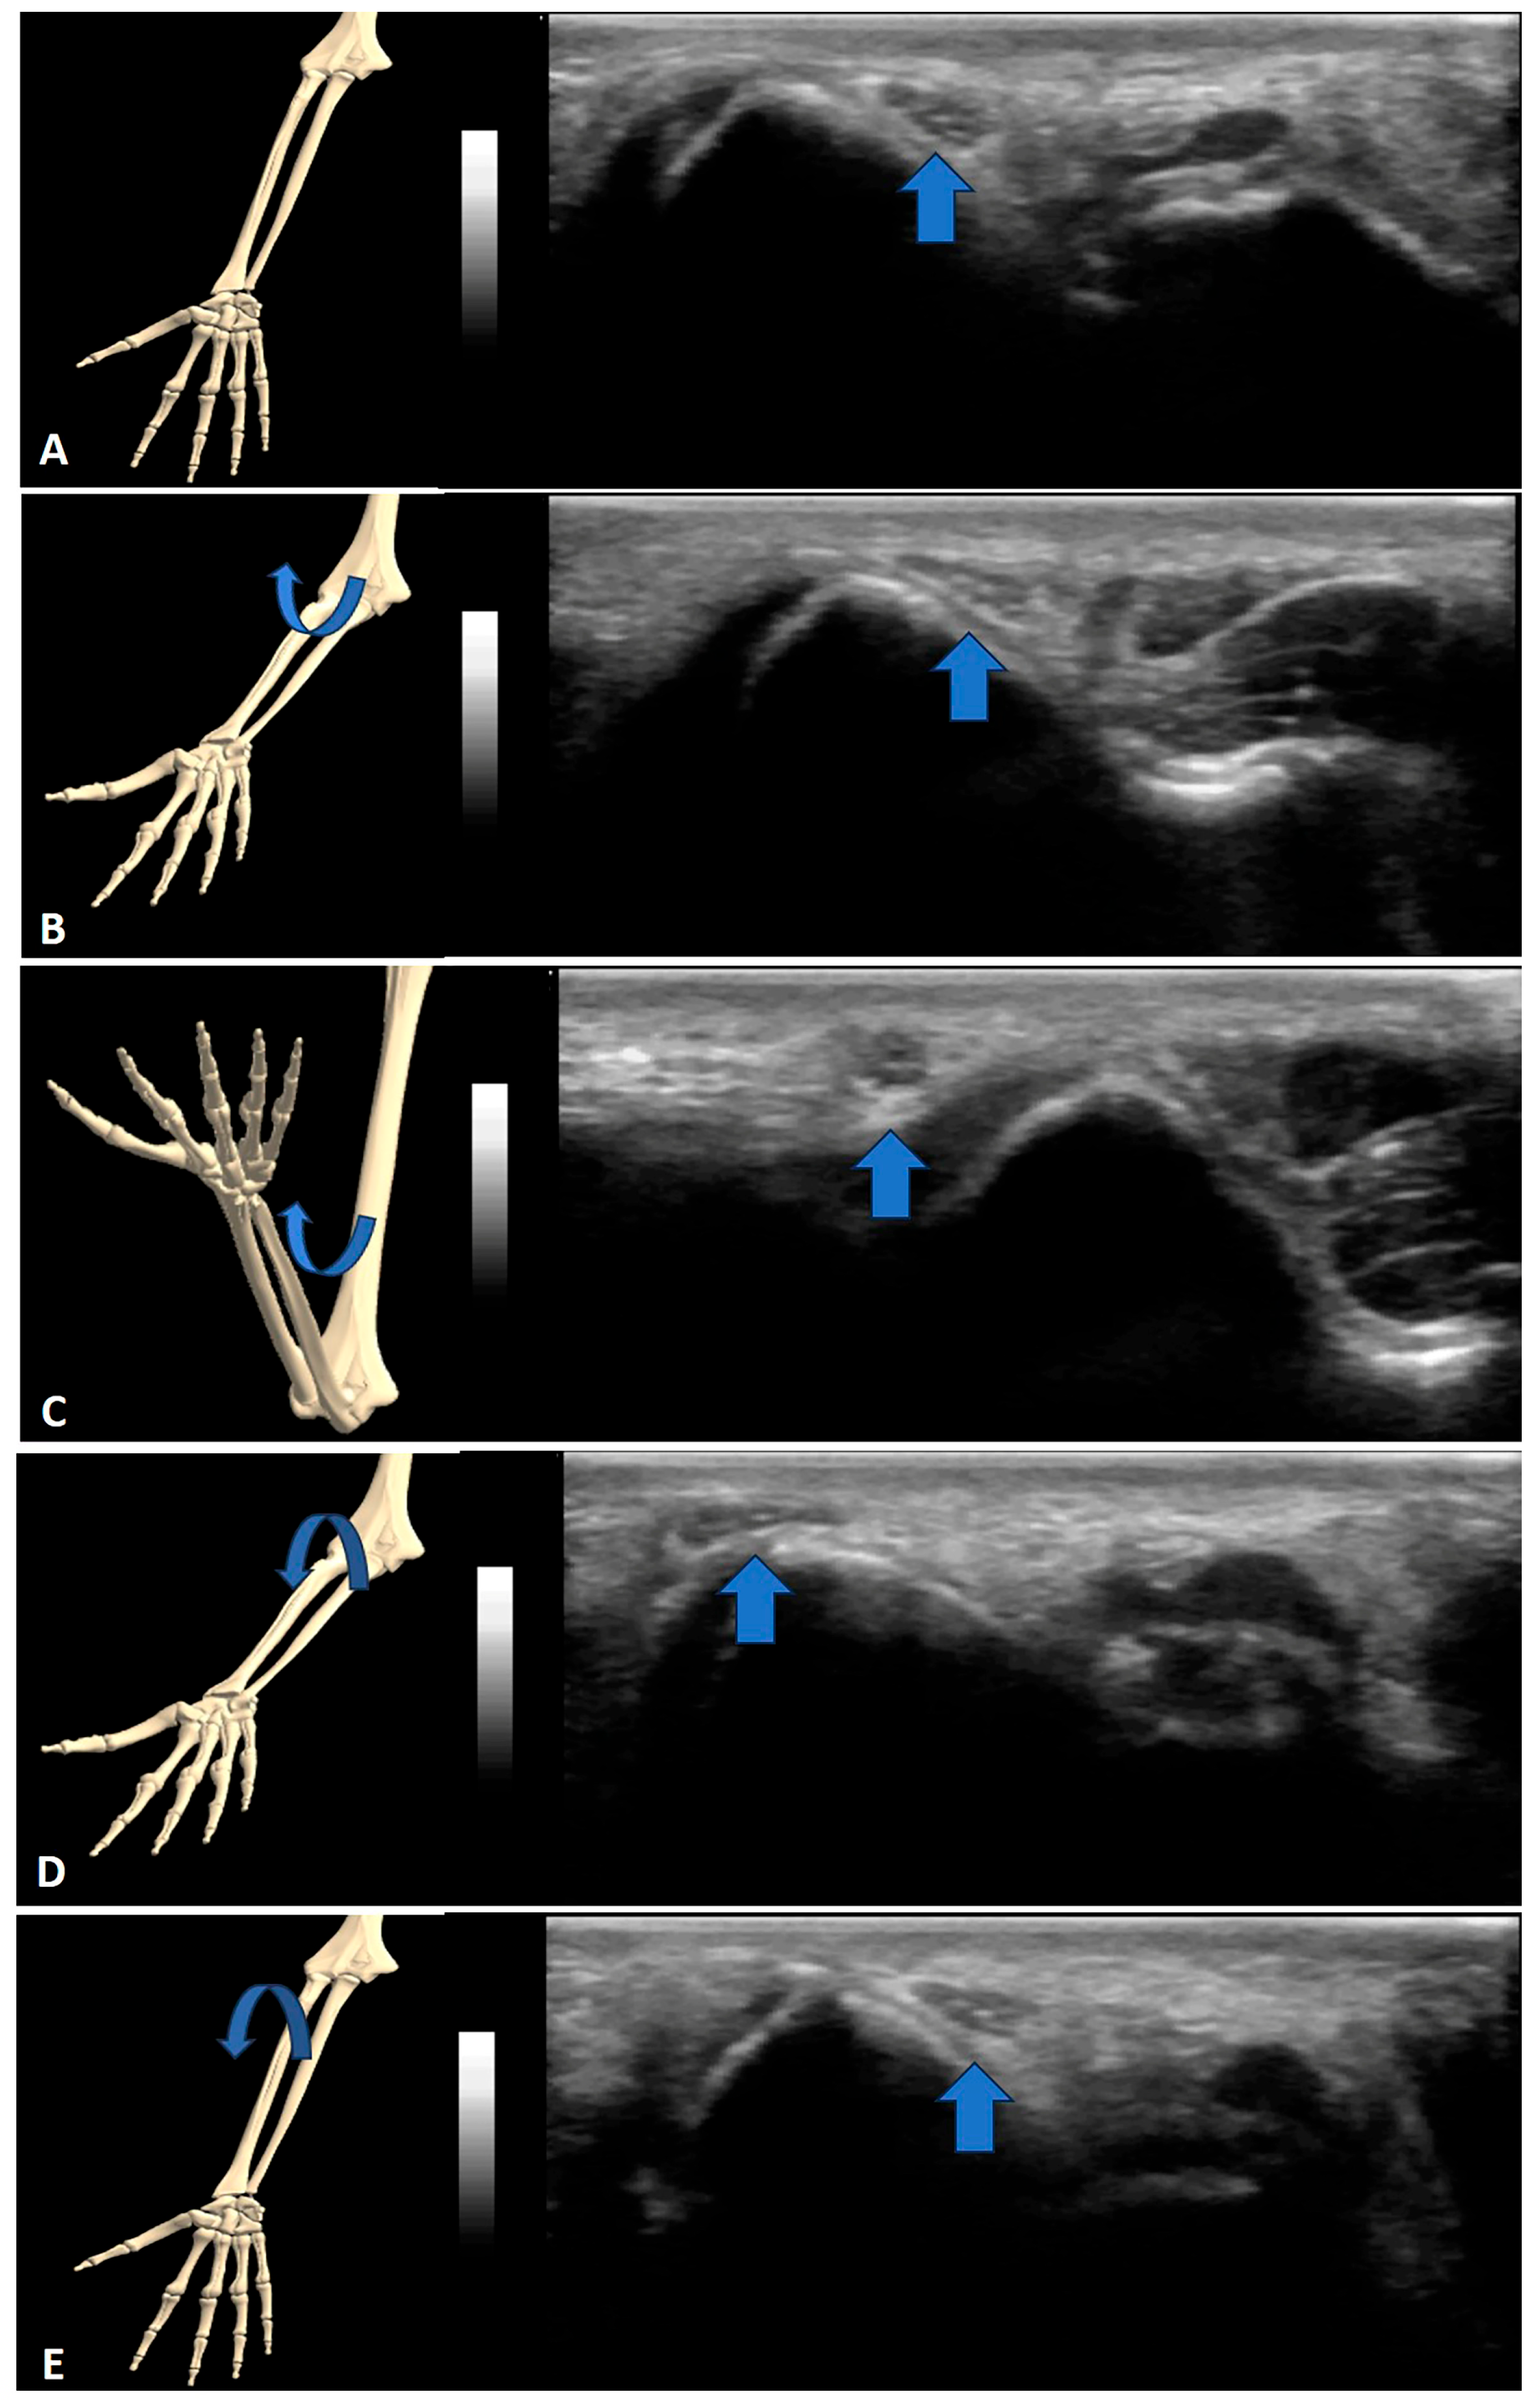

3. Results

4.1. Nerve Snapping

4.2. Tendon Snapping